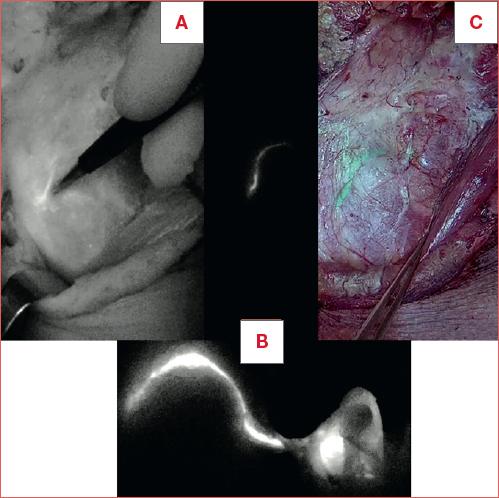

Patients were placed in supine position with the head approximately in the same position as that of the surgery. Dynamic acquisitions started immediately after radiocolloid administration and continued for 15 minutes (30 frames/sec), while static images, in anteroposterior and lateral projections, were acquired 30 minutes and 2 hours following the injections. At the end of the lymphoscintigraphic procedure, the skin projection of the underlying enhancing lymph nodes was marked with India ink. Scintigrafic data were matched to CT images in order to achieve a topografic localisation of the interested lymphatic drainage on both coronal and axial CT scans (Fig. 1).

Figure 1. Preoperative detection of SPECT/CT lymphoscintigraphic enhancing lymph node.